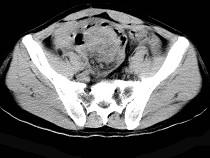

问题 58岁,间断腹部隐痛9个月,贫血3个月,近日加重并伴有柏油样便,CT所见如图,最可能诊断是()

选项 A.小肠淋巴瘤 B.小肠恶性间质瘤 C.小肠重复畸形 D.小肠癌 E.小肠淋巴肉瘤

答案 E